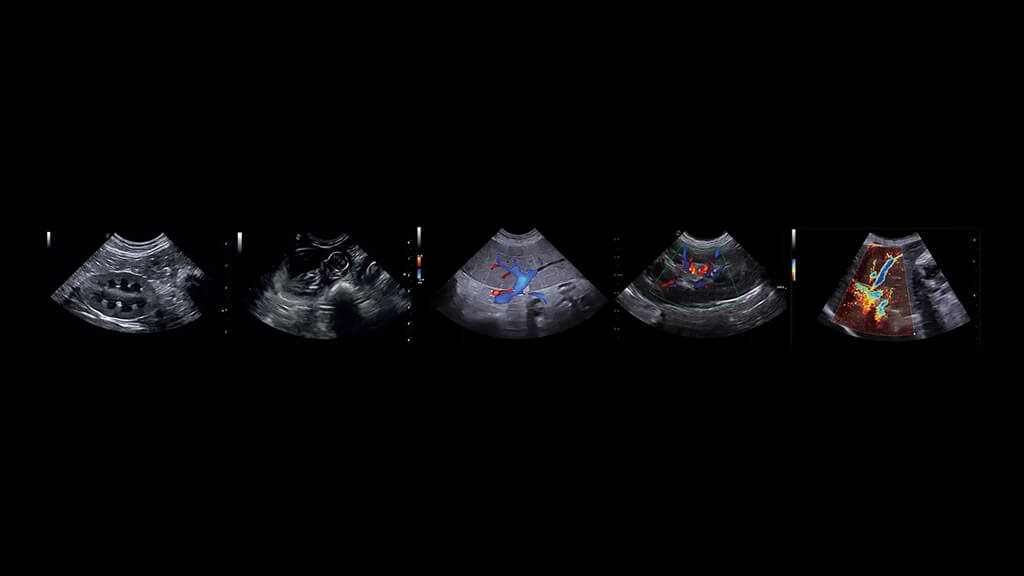

Ekokardiyografi (EKO), veteriner hekimlikte kalp hastalıklarının tanısı, derecelendirilmesi ve takibinde kullanılan en değerli görüntüleme yöntemlerinden biridir. Yüksek frekanslı ses dalgaları ile kalbin kapaklarını, odacıklarını, kas yapısını ve kan akımını gerçek zamanlı değerlendirmeye olanak sağlar.

Neden Ekokardiyografi?

Ekokardiyografi; doğru tanı ve etkin tedavi yönetimi açısından büyük avantaj sağlar: